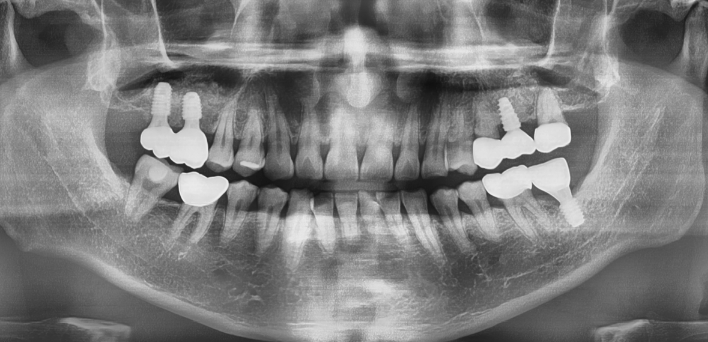

임플란트 : 손 ** 님 (50대)

Before Before

2020.02.30

After After

※ 더서울치과의원은 의료법을 준수하며 위 케이스는 실제 환자의 동의를 얻은 사례로 치료 전, 후가 동일한 환경에서 촬영되었습니다.

환자 케이스에 따라 부작용이 발생할 수 있습니다. 이 부분은 의료진의 충분한 상담과 체크를 통해 예방하고 줄일 수 있습니다.

[임플란트 부작용] 수술 후 관리가 소홀할 경우 출혈, 주위염 등의 부작용이 발생할 수 있어 구강 위생을 철저히 유지하고, 정기적인 검진을 통해 상태를 점검하는 것이 중요합니다.

환자 특징

환자 특징01무치악 상태

환자 특징02수년간 무치악으로 지내심

임플란트가 불가능할것이라

생각하고 내원

위, 아래 6개씩 식립

디지털 풀아치 임플란트